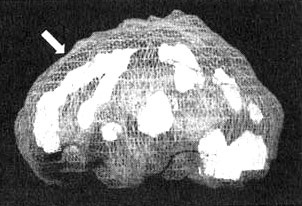

Мозг «яростного водителя»

Иллюстрация к книге — Измените свой мозг - изменится и жизнь! [i_059.jpg]

Трехмерное изображение — активный мозг. Обратите внимание на выраженное усиление активности в поясной извилине (см. стрелку).